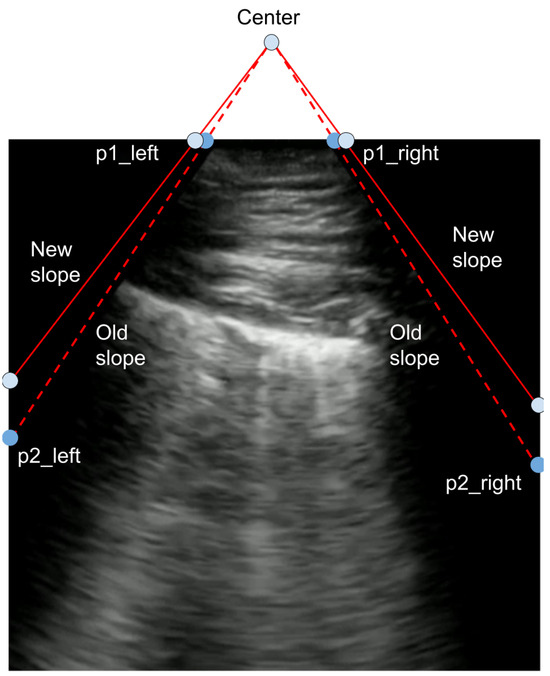

If the bounds of the viewing window are known, then the POCUS image can be transformed to have various different angles by remapping the corners of the viewing window. To obtain these labels, the boundaries are first approximately labeled manually. Those labels are then processed to ensure that the absolute slope of the left and right boundaries are the same and that the left and right points lie on the same horizontal axis. This symmetry makes the image transformations significantly easier. This point remapping process is shown in Figure 3. Here, new points for each corner of the viewing window are randomly selected, and a transformation matrix is defined accordingly. Specifically, the corners of the original viewing window can be used to find both a center and a slope. A new slope is then randomly sampled based on the original slope. While keeping the center point constant, the new slope is then used to find the corners of the viewing window.

Figure 3. To generate a random transformation: 1. Using the labeled bounds of a convex ultrasound image defined by the corner points { p 1 left , p 2 left , p 1 right , p 2 right } , find a new slope based on the distribution N ( old _ slope , σ ) . 2. Define new points { p 1 left , p 1 right } using the new slope and constant center point. 3. Estimate a transformation matrix based on the new and old set of corner points.